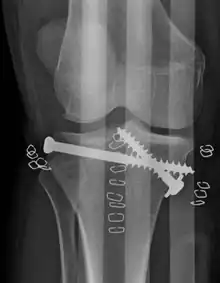

| A severe tibial plateau fracture with an associated fibular head fracture | |

Pain may be managed with NSAIDs, opioids, and splinting.[2][3] In those who are otherwise healthy, treatment is generally by surgery.[2] Occasionally, if the bones are well aligned and the ligaments of the knee are intact, people may be treated without surgery.[3] The surgery usually involves reducing the fractured fragments of the tibia plateau to their anatomical position and fixing them in place with screws only or fixed angle anatomical plates ensuring absolute stability. Implant selection is based on the type of injury. Generally, simple or incomplete fractures (Schatzker type 1) of the plateau are compressed with 6.5mm partially threaded cancellous screws. Complex type fractures will require a plate for enhanced stability. As the tibia condyles articulate with the femur (thigh bone) to form knee joint, any incongruity in the articular surface is unacceptable as it leads to early arthritis. Prolonged immobilization of the knee joint is also not recommended which result in stiffness of the joint and difficult recovery.